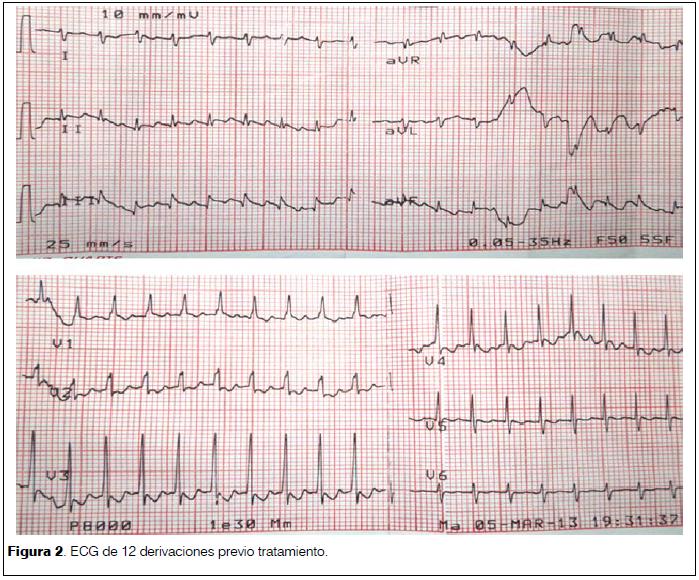

Electrocardiograma (ECG) de 12 derivaciones: ritmo regular, 230 lpm, complejo QRS finos, ausencia de onda P, onda T sin trastornos de la repolarización (figura 2).

Se realizó adenosina no retomando ritmo sinusal, objetivando como se ve en la figura 3 espaciamiento de los complejos QRS y la presencia de ondas en dientes de sierra características del flutter auricular, se realizó entonces cardioversión eléctrica sincronizada con 5 J, efectiva, revirtiendo a ritmo sinusal (figura 4).